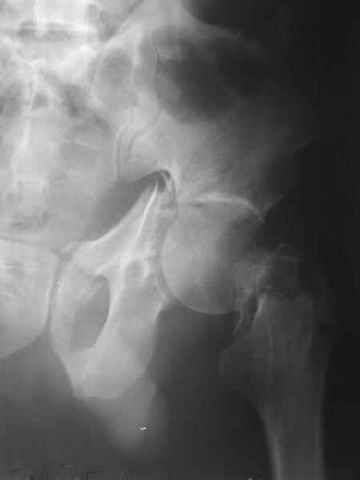

Контрольный снимок перед разрешением нагрузки прямой 13/10/03

Перед разрешением нагрузки боковой 13/10/03

Больной 18 мая 2003 года в автоаварии получил перелом левой вертлужной впадины, вывих бедра. Госпитализирован в один из стационаров области.Вывих вправлен. В последствии бедро вывихивалось еще дважды. На консультацию был представлен снимок от 19.05.03г., больной переведен к нам 3.06.03г. Снимок при поступлении - перелом впадины, задне-верхний вывих бедра. 05.06.2003 г. выполнено открытое вправление вывиха левого бедра и остеосинтез стенки вертлужной впадины двумя винтами. Послеоперационный период без осложнений. Объем движений в левом тазобедренном суставе восстановился полностью. Выписан на амбулаторное лечение в удовлетворительном состоянии с рекомендациями 3 месяца ходить на костылях без нагрузки на оперированную конечность. На контрольных рентгенограммах левого тазобедренного сустава 13.10.2003 г. - признаки консолидации перелома; плотность, форма головки и состояние суставных поверхностей удовлетворительные. Разрешена дозированная осевая нагрузка, на конечность с использованием дополнительной опоры. 19.12.2003 г. больной обратился с жалобами на боли в левом тазобедренном суставе. На рентгенограммах левого тазобедренного сустава 19.12.2003 г., 20.02.04г. - асептичекий некроз головки бедра. 5.04.04г. - эндопротез. Сейчас ходит без трости, не хромает. Особенность эндопротезирования - при удалении винтов прослежена линия перелома заднего края впадины и предложено установить чашку несколько меньшего диаметра, чтобы она была покрыта несломанной частью.